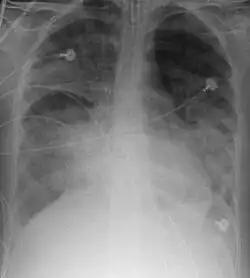

X-ray

Chest X-ray is the most common method used for diagnosis,[42] and may be used to confirm a diagnosis already made using clinical signs.[23] Consolidated areas appear white on an X-ray film.[47] Contusion is not typically restricted by the anatomical boundaries of the lobes or segments of the lung.[31][48][49] The X-ray appearance of pulmonary contusion is similar to that of aspiration,[36] and the presence of hemothorax or pneumothorax may obscure the contusion on a radiograph.[29] Signs of contusion that progress after 48 hours post-injury are likely to be actually due to aspiration, pneumonia, or ARDS.[13]

Although chest radiography is an important part of the diagnosis, it is often not sensitive enough to detect the condition early after the injury.[40] In a third of cases, pulmonary contusion is not visible on the first chest radiograph performed.[10] It takes an average of six hours for the characteristic white regions to show up on a chest X-ray, and the contusion may not become apparent for 48 hours.[10][31][48] When a pulmonary contusion is apparent in an X-ray, it suggests that the trauma to the chest was severe and that a CT scan might reveal other injuries that were missed with X-ray.[2]

Computed tomography

Computed tomography (CT scanning) is a more sensitive test for pulmonary contusion,[8][38] and it can identify abdominal, chest, or other injuries that accompany the contusion.[43] In one study, chest X-ray detected pulmonary contusions in 16.3% of people with serious blunt trauma, while CT detected them in 31.2% of the same people.[50] Unlike X-ray, CT scanning can detect the contusion almost immediately after the injury.[48] However, in both X-ray and CT a contusion may become more visible over the first 24–48 hours after trauma as bleeding and edema into lung tissues progress.[51] CT scanning also helps determine the size of a contusion, which is useful in determining whether a patient needs mechanical ventilation; a larger volume of contused lung on CT scan is associated with an increased likelihood that ventilation will be needed.[48] CT scans also help differentiate between contusion and pulmonary hematoma, which may be difficult to tell apart otherwise.[52] However, pulmonary contusions that are visible on CT but not chest X-ray are usually not severe enough to affect outcome or treatment.[42]